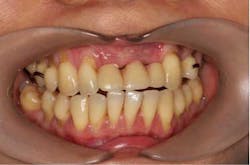

A 43-year-old female with a noncontributory medical history taking no medication and having no known food/drug allergies presented to my general dental office with a chief complaint of having “loose teeth with an underbite.” Clinically, she had generalized, moderate, chronic periodontal disease and was missing teeth Nos. 8 through 10. She had a Class III malocclusion with pathologic flaring of her remaining anterior teeth. She had both vertical and horizontal tissue loss in the No. 8 through 10 region. The patient wore a transitional partial denture to replace the anterior missing teeth that was placed in edge-to-edge occlusion by her previous dentist. (Fig. 1) She did not like having a removable prosthetic and desired a fixed option in the form of implants to replace her missing teeth. I sent her to the periodontist for a periodontal consult for her remaining dentition and dental implants to replace her missing front teeth.